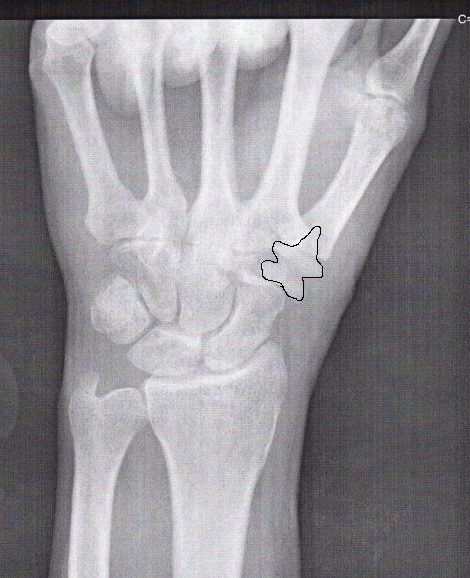

Here I have (roughly) outlined the appliance. This is exactly the same x-ray as the one above, so you can see the shape of the appliance here and then look for it in the second picture. |